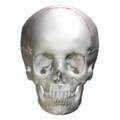

The coronal suture is a dense, fibrous connective tissue joint that separates the frontal and parietal bones of the skull. At birth, the bones of the skull do not meet.